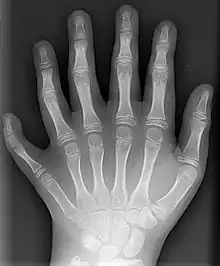

Selon le type de malformation (et son caractère primaire ou secondaire), elle est découverte lors du diagnostic prénatal ou à la naissance voire plus tard. Il existe des malformations majeures et mineures. Les malformations majeures donnent à l'individu un handicap très grave voire causent sa mort. Les malformations mineures (exemple : brachymétatarsie) n'ont pas de conséquences sérieuses pour l'individu.

Il existe une grande variété de malformations : de la simple disgrâce mineure aux malformations sévères qui conduisent à la mort, in utero parfois. Les malformations sont uniques ou multiples, symétriques ou non, accidentelles ou d'origine génétique. Elles sont presque toujours congénitales ou « constitutionnelles »[1]. On distingue généralement :

- les malformations primaires (aussi dites "vraies") ; repérées chez 2 % des enfants nés vivants et chez 12 à 14% des mort-nés, mais le taux réel est plus important car toutes ne sont pas repérées ou déclarée[1] (il existe peu de registres des malformations et certaines anomalies restent cachées la vie durant du patient) ;